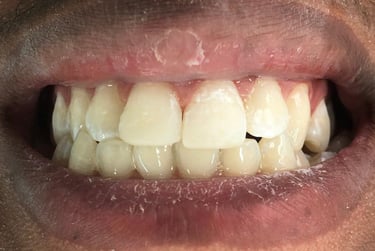

Cirurgia de aumento de coroa clínica antes das coroas

Caso que demonstra a vantagem da integração de diversas áreas da odontologia, unindo cirurgia, periodontia, prótese e estética para alcançar resultados funcionais e harmônicos.

Antes